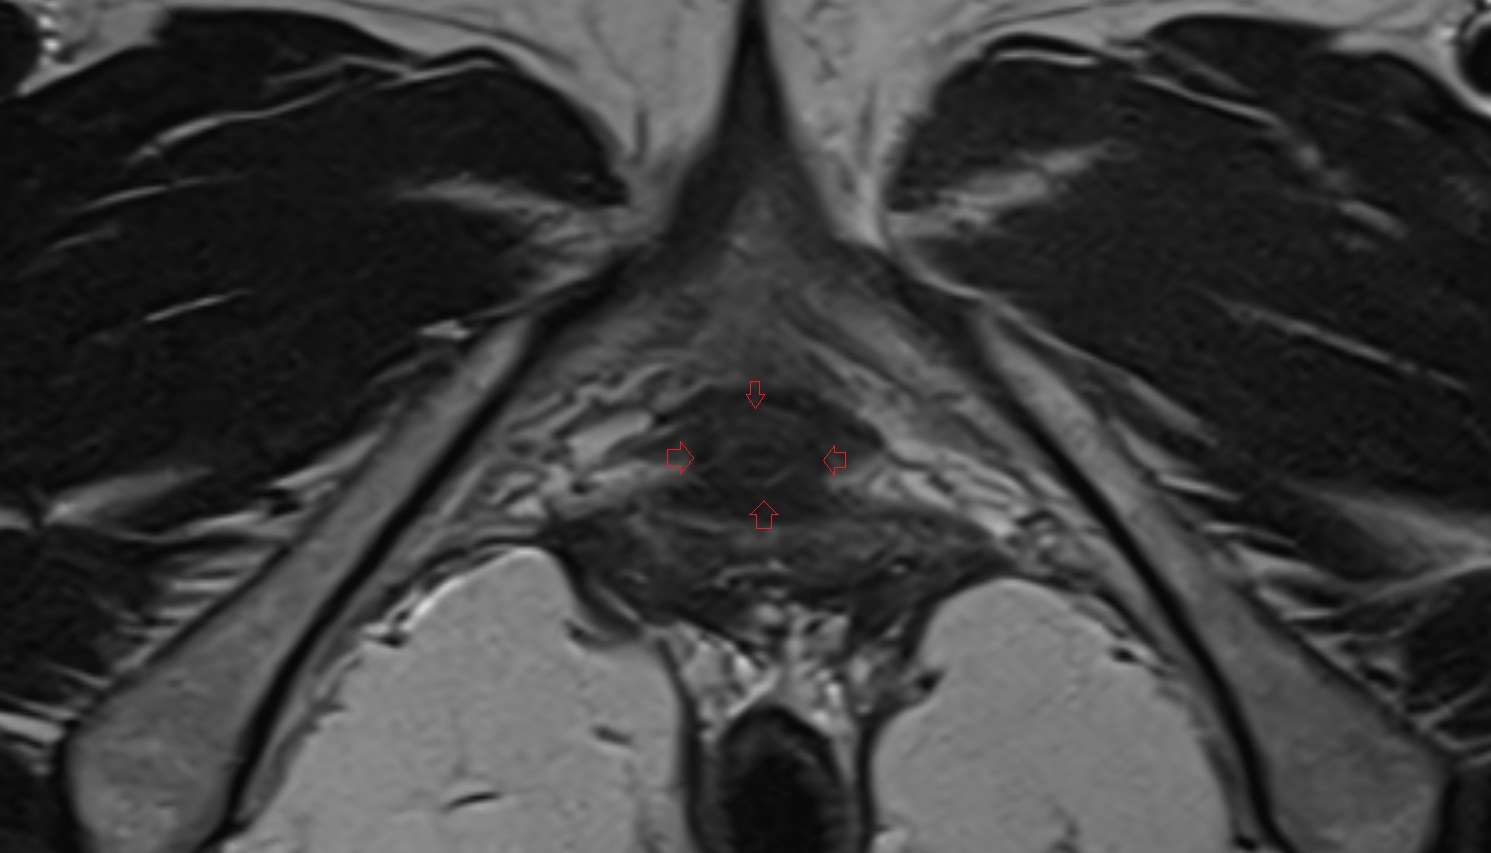

- Peripheral zone of prostate

- Anterior Fibromuscular Stroma of prostate

- Central zone of prostate

- Transitional zone of prostate